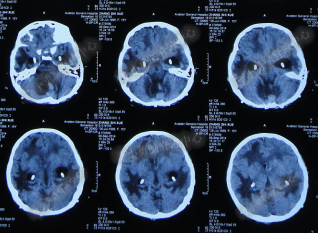

腰大池持续引流20天内,体温仍间断高热,曾3次脑脊液细菌培养均示鲍曼不动杆菌,先后使用利奈唑胺+克倍宁,利奈唑胺+克倍宁+奥硝唑,舒普深+米诺环素+来立信+氟康唑,舒普深+米诺环素+美罗培南+氟康唑,及日达仙、人免疫球蛋白提高免疫力,但颅内感染仍控制不住,期间多次头部CT检查均示脑室无明显扩张(图-7、图-8、图-9)。

图-7:2014年6月9日头部CT

图-8:2014年6月14日头部CT

图-9:2014年6月21日头部CT